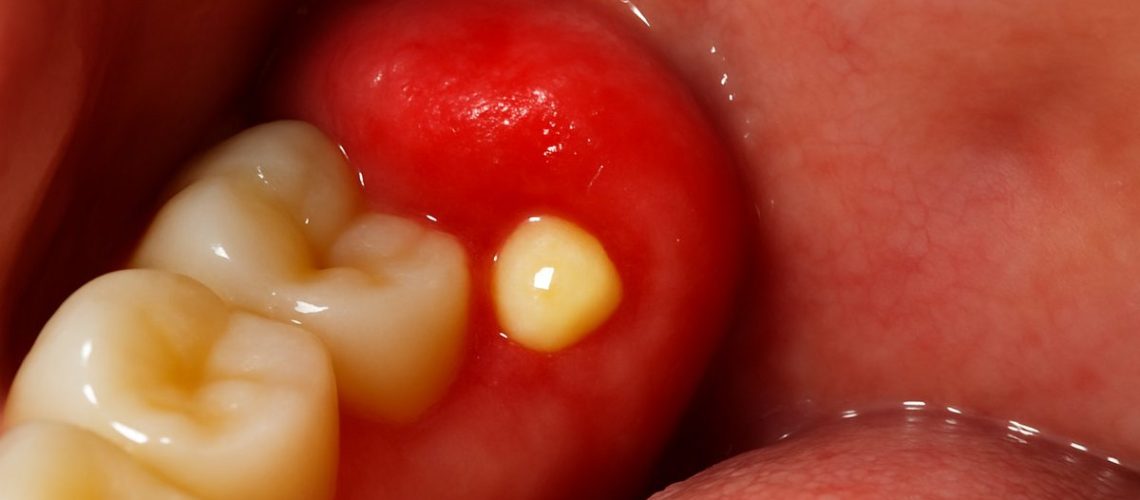

You might notice localized swelling or a raised flap of gum tissue (an operculum) over a partially erupted tooth. The tissue can be red and tender. This happens when the tooth breaks the surface unevenly, leaving an area where food and bacteria can collect.

Bad taste, bad breath, or pus drainage

If food gets trapped under a gum flap, bacteria can build up, leading to a bad taste or persistent bad breath. In some cases, you may see or taste a small amount of pus. These signs point to trapped debris and early infection under the gum.

Visible pus or rapidly spreading swelling

Pus, increasing redness, or swelling that spreads quickly beyond the immediate area are urgent signs. Rapid progression risks deeper tissue infection and may need antibiotics plus a surgical visit to drain or remove the source.